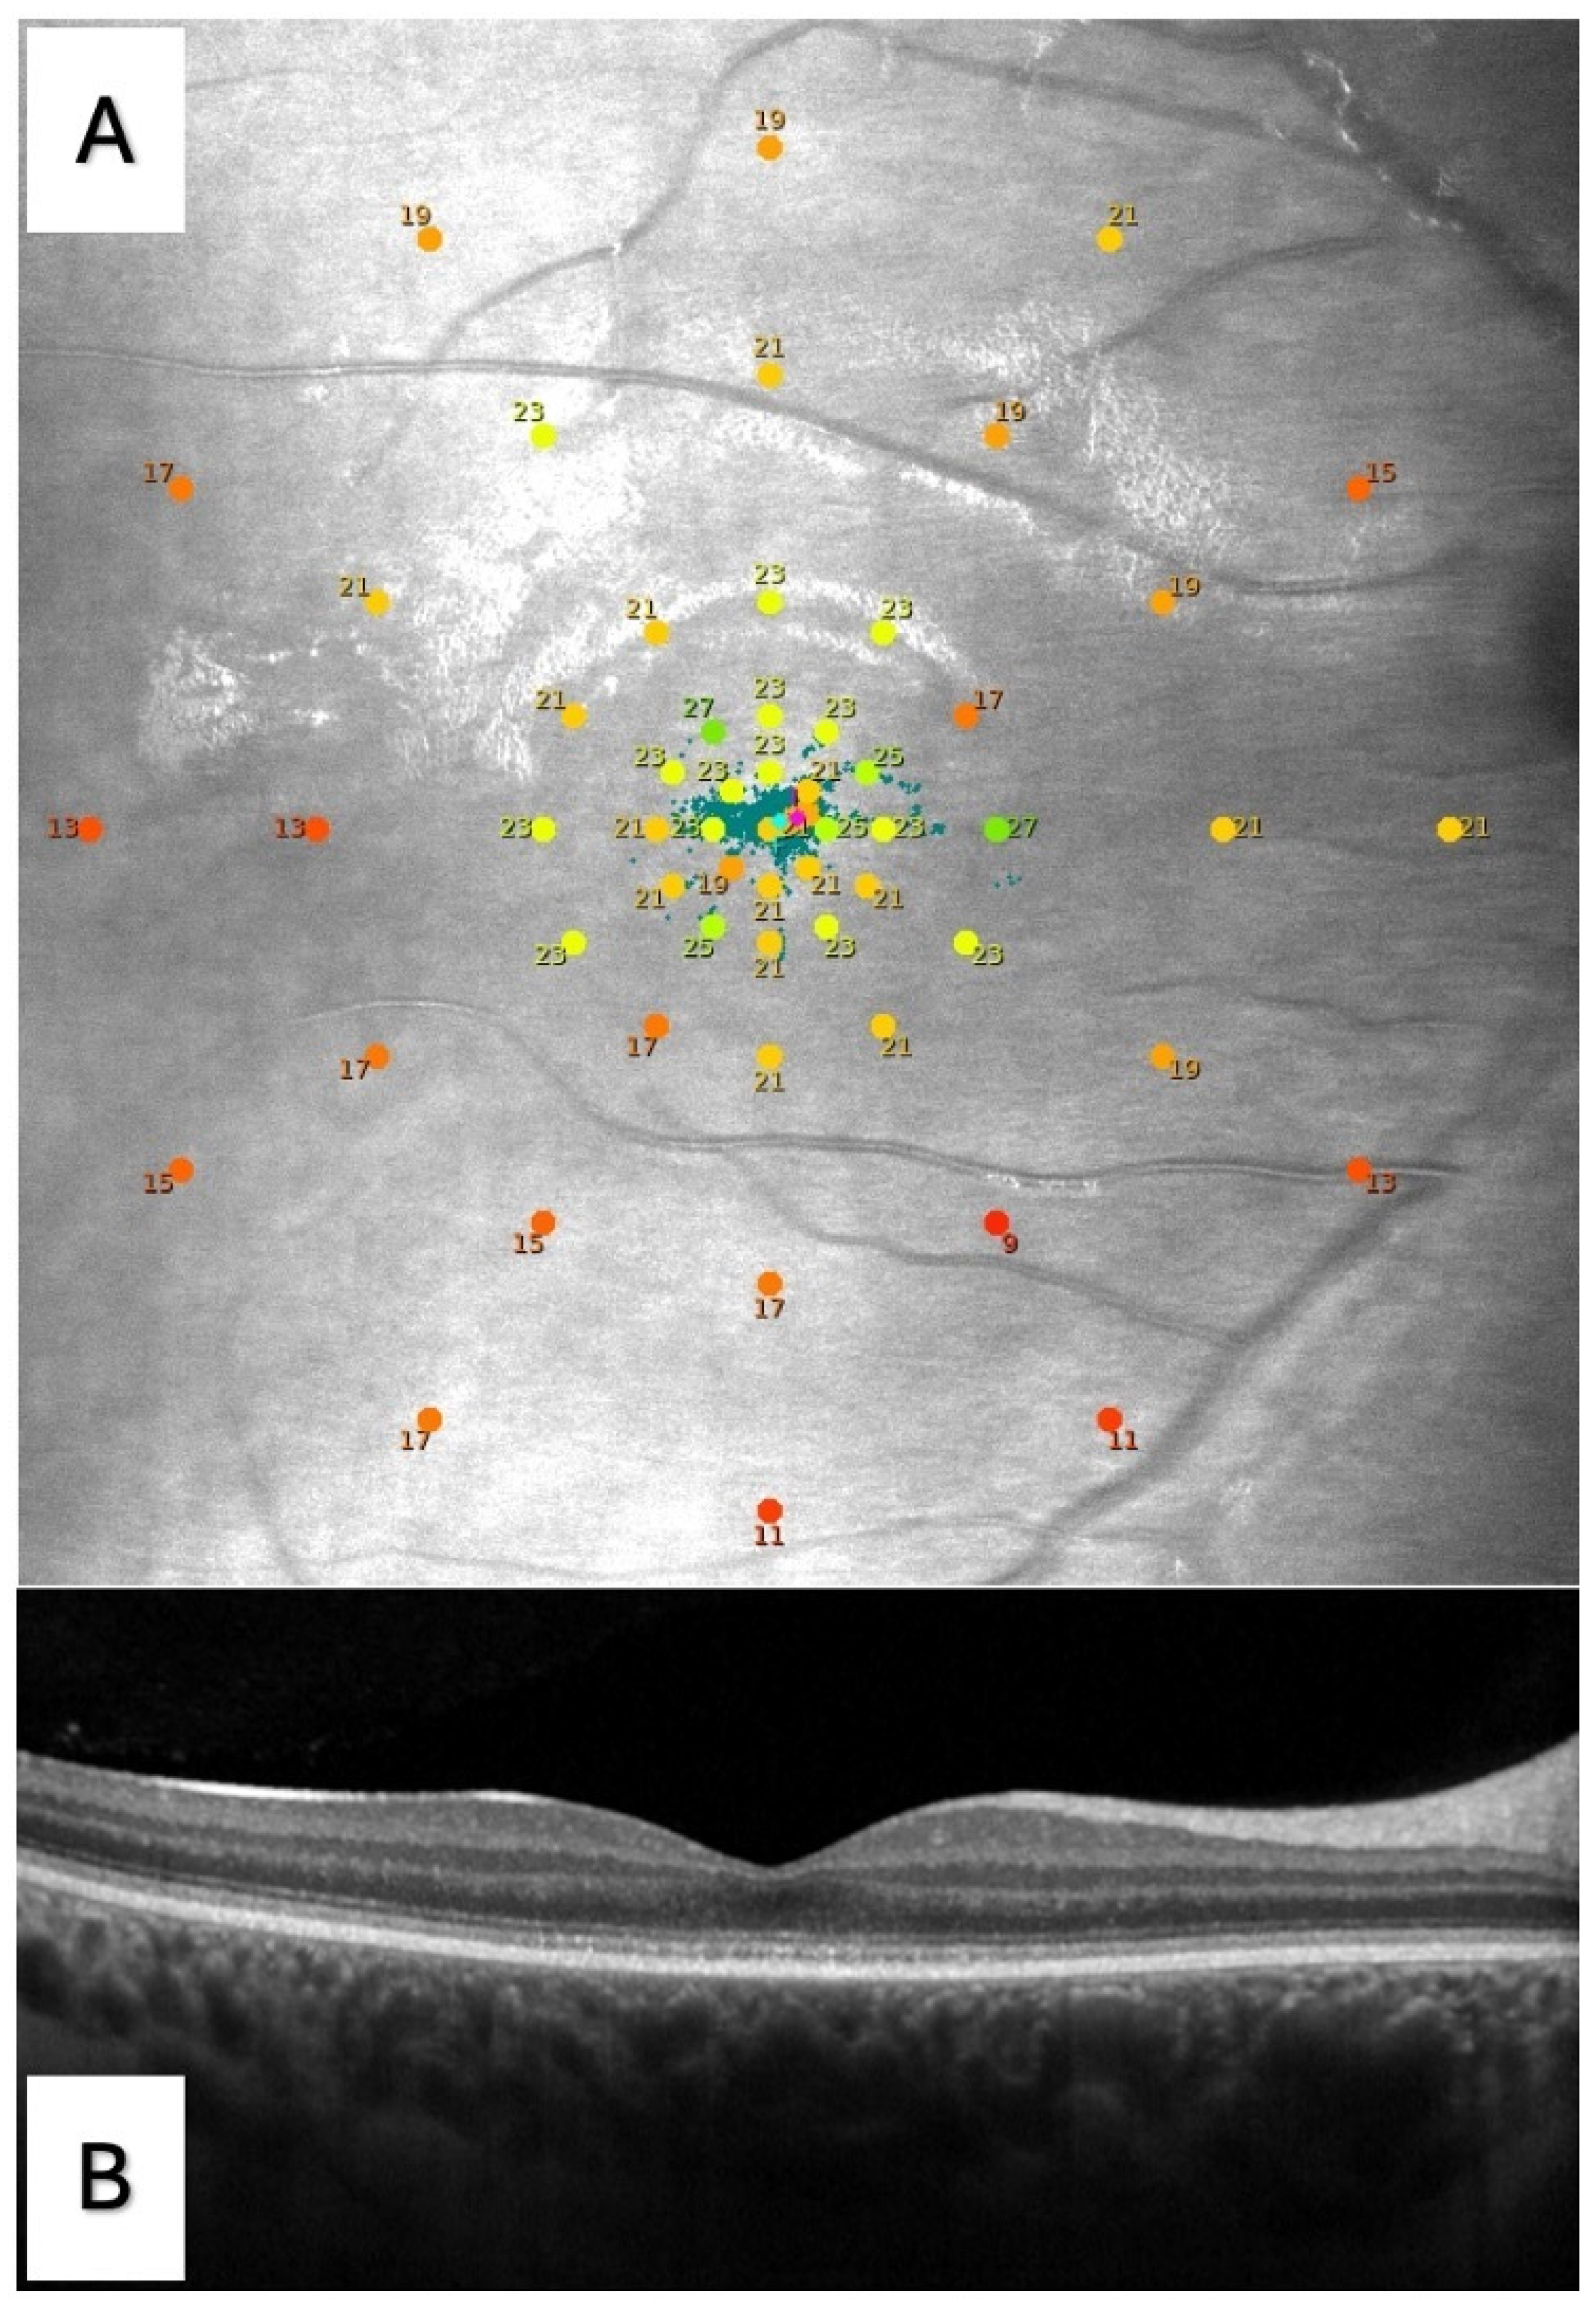

2.3. Microperimetry

2.4. Optical Coherence Tomography